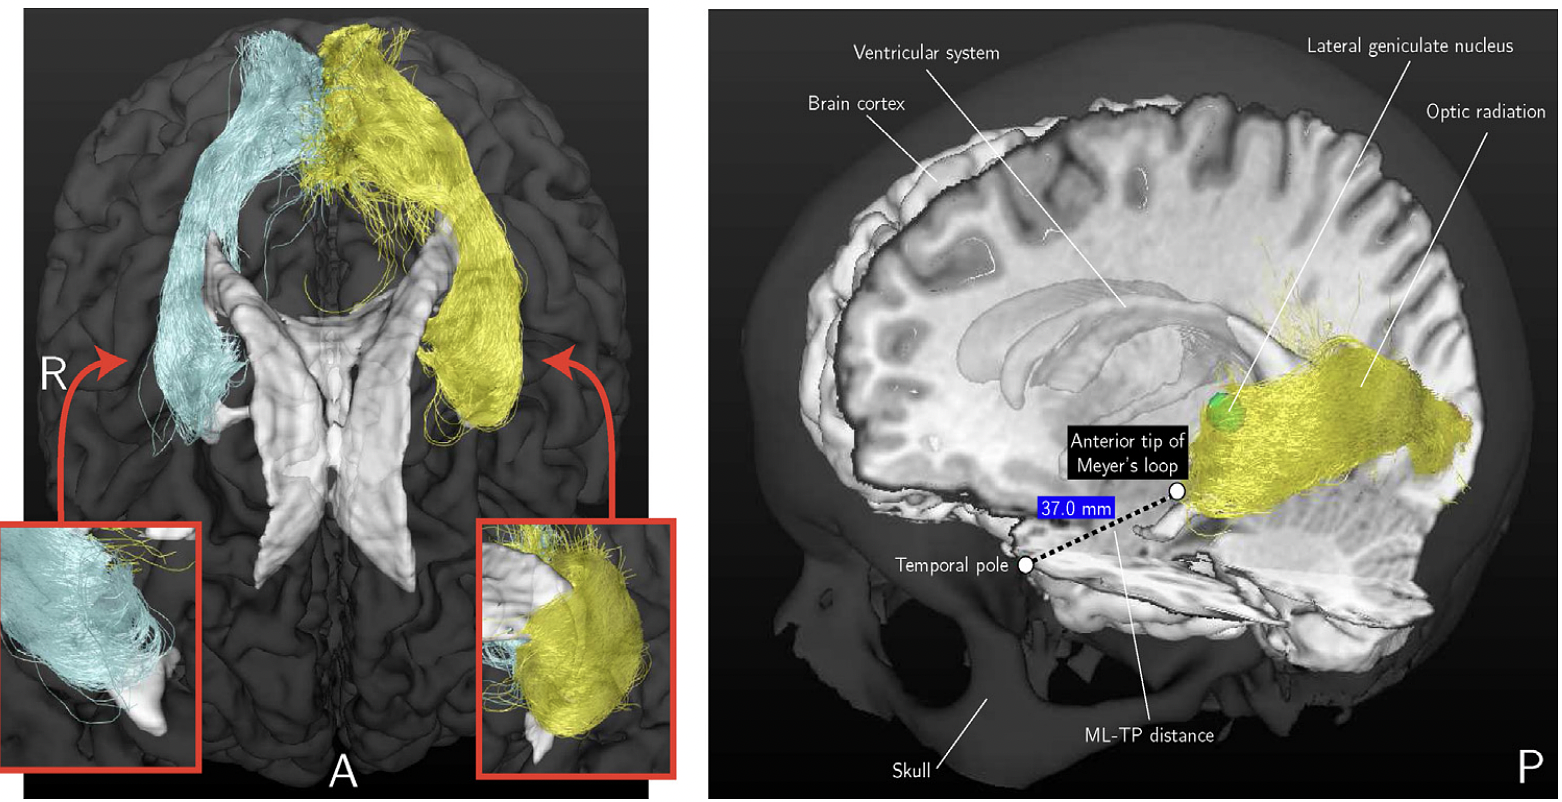

Left: An example of the reconstruction result of the OR using probabilistic tractography from an axial view. As inserts, close-ups are shown of the anterior tips of the reconstructions of the OR from a coronal view. Right: The tracking results are shown for the same volunteer in a composite image along with other brain structures such as the ventricular system. The ML-TP distance measurement is indicated.

An accurate delineation of the optic radiation (OR) using diffusion MR tractography may reduce the risk of a visual field deficit after temporal lobe resection. However, tractography is prone to generate spurious streamlines, which deviate strongly from neighboring streamlines and hinder a reliable distance measurement between the temporal pole and the Meyer's loop (ML-TP distance). Stability metrics are introduced for the automated removal of spurious streamlines near the Meyer's loop. Firstly, fiber-to-bundle coherence (FBC) measures can identify spurious streamlines by estimating their alignment with the surrounding streamline bundle. Secondly, robust threshold selection removes spurious streamlines while preventing an underestimation of the extent of the Meyer's loop. Standardized parameter selection is realized through test-retest evaluation of the variability in ML-TP distance. The variability in ML-TP distance after parameter selection was below 2 mm for each of the healthy volunteers studied (N = 8). The importance of the stability metrics is illustrated for epilepsy surgery candidates (N = 3) for whom the damage to the Meyer's loop was evaluated by comparing the pre- and post-operative OR reconstruction. The difference between predicted and observed damage is in the order of a few millimeters, which is the error in measured ML-TP distance. Comparison with existing method(s) The stability metrics are a novel method for the robust estimate of the ML-TP distance. The stability metrics are a promising tool for clinical trial studies, in which the damage to the OR can be related to the visual field deficit that may occur after epilepsy surgery.